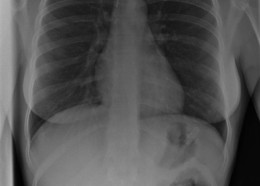

Чудни ренгенски снимки